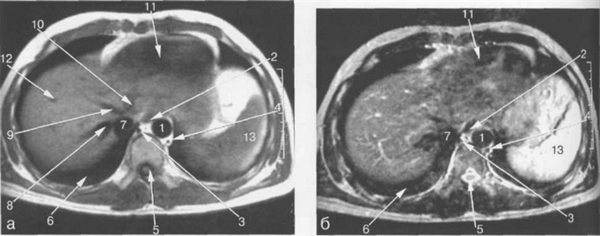

МРТ АНАТОМИЯ СЕЛЕЗЕНКИ

Неизмененная селезенка на Т1-ВИ имеет несколько большее время релаксации, чем паренхима печени, и характеризуется изоинтенсивным сигналом, более низким по сравнению с сигналом от печени. На Т2-ВИ селезенка имеет подчеркнуто высокую интенсивность сигнала и визуализируется как структура с более высокой интенсивностью сигнала по сравнению с печеночной паренхимой. Интенсивность сигнала селезенки соответствует параметрам кортикального слоя почек (см. рис. 11.9—11.12).

Рис. 11.24. MPT брюшной полости в аксиальной плоскости на уровне надпочечников.

а-Т1-ВИ;б-Т2-ВИ.

1 — аорта; 2 — нижняя полая вена; 3 — селезеночная артерия; 4 — общая печеночная артерия; 5 — чревный ствол; 6 — левый надпочечник; 7 — правый надпочечник; 8 — левая почка; 9 — желчный пузырь; 10 — Бертиниевы столбы левой почки.

Сосуды ворот селезенки хорошо видны во всех импульсных последовательностях (рис. 11.24). Селезеночная вена определяется как структура продолговатой формы, которая зачастую имеет горизонтальное расположение (см. рис. 11.12). Селезеночная вена используется в качестве ориентира для локализации хвоста и тела поджелудочной железы, которые располагаются кпереди от нее (см. рис. 11.12, 11.14). В области ворот внутриселезеночные сосуды видны как разветвляющиеся продолговатые структуры.